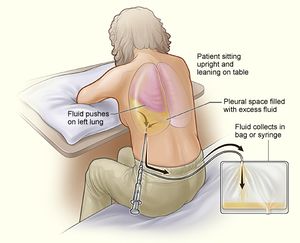

بزل الصدر

عندما يشتبه بوجود كمية زائدة من السائل في الجوف الجنبي أو حدوث انصباب رئوي، وعند التأكيد على موقع هذا السائل يتم أخذ عينة من هذا السائل للفحص.[11] الإجراء الذي يتم من خلاله إزالة السائل من الصدر يطلق عليه بزل الصدر التحليلي.[12] يقوم الطبيب بإدراج إبرة صغيرة أو أنبوب بلاستيكي مجوف في جدار الصدر و يقوم بسحب السائل.[13]

يمكن إجراء بزل الصدر في مكتب الطبيب أو في المشفى. يستخدم الصوت الفائق هنا لإرشاد الإبرة إلى السائل المحصور في تجاويف صغيرة حول الرئتين.

بزل الصدر لا يسبب مضاعفات خطيرة في العادة. بشكل عام تؤخذ صورة الأشعة السينية للصدر بعد إجراء بزل الصدر لتقييم حالة الرئتين. بعض المضاعفات المحتملة لبزل الصدر تتضمن ما يلي:

- أثناء إجراء بزل الصدر يتم إدراج إبرة أو أنبوب بلاستيكي رفيع و مجوف خلال أضلاع الصدر من الخلف حتى تصل جدار الصدر. يتم إرفاق محقان لسحب السائل خارجًا من الصدر. يمكن من خلال هذا الإجراء إزالة 6 أكواب (1.5 لتر) من السائل في كل مرة.